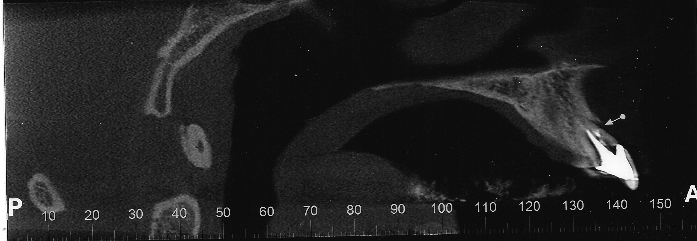

Tomografia Arcada Superior

ImgArcadaDentaria.png